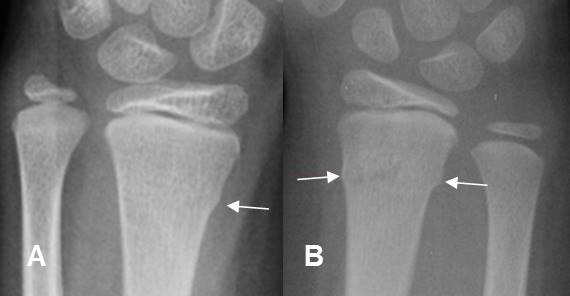

Fig 179. Fractura en torus.

A: y B: Rx AP. Cortical “arrugada en el tercio distal del radio, por fracturas en torus.

Fig 180. Fractura de Colles.

A: y B: Rx lateral de muñeca. Fractura de Colles, con desplazamiento posterior del fragmento distal del radio.